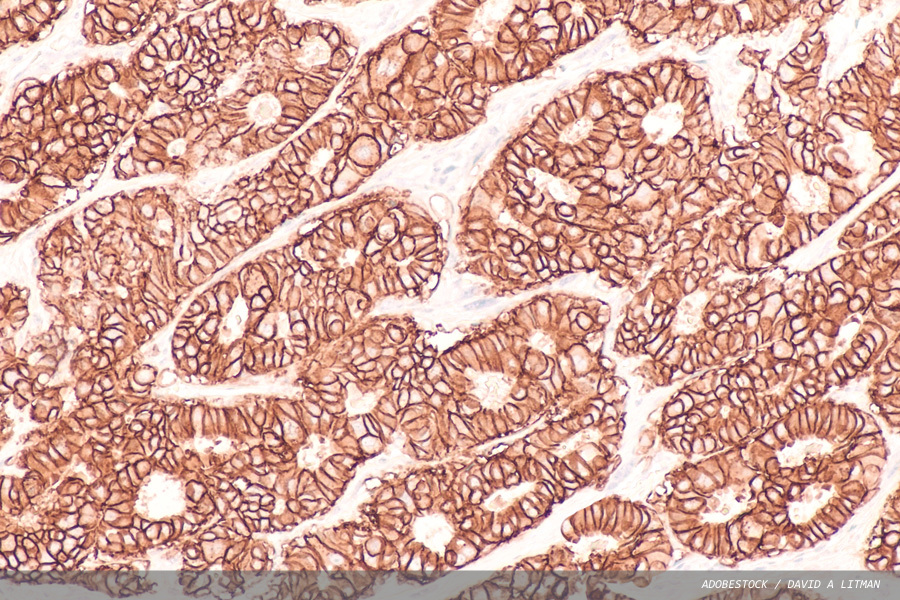

University of Warwick research warns that popular deep learning systems trained for cancer pathology may be relying on hidden shortcuts rather than genuine biological signals.

Early-onset colorectal cancer: an increasing healthcare issue

Historically, colorectal cancer was seen as a disease of later life. More recently, however, the increased incidence of cancer affecting the lower intestinal tract in the younger age group has been reported. Here, Pathology in Practice Science Editor Brian Nation looks at a selection of current research focusing on this emerging healthcare...